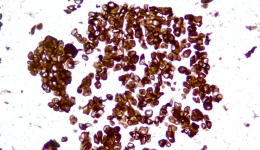

Description CLDN18.2是Claudin蛋白質(zhì)家族的一員,位于細(xì)胞膜表面,Claudin18.2(CLDN18.2)表達(dá)具有特異性。其作為Claudins蛋白的一個(gè)亞型,在正常組織中僅表達(dá)于分化的胃黏膜上皮細(xì)胞。在胃癌、食管癌和胰腺癌等多種腫瘤中表達(dá),并且不僅限于原發(fā)病灶,在轉(zhuǎn)移灶中也有表達(dá)。目前臨床研究中使用的檢測方法均為免疫組化。

示例

IHC染色結(jié)果